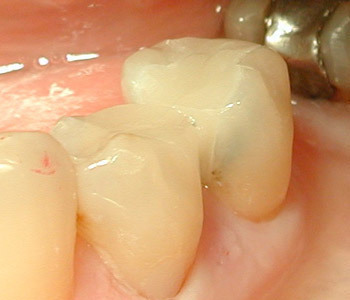

- Cas 1 : 2 prémolaires inférieures - 1 séance de 90 minutes